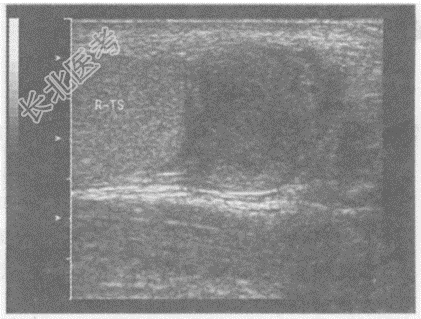

- 单项选择题临床资料:男, 23岁,自述右侧阴囊疼痛伴发热2天。

化验检查: 血常规WBC升高。

超声综合描述:右侧睾丸形态、大小正常, 内回声均匀。右侧附睾尾回声减低,范围: 4.1cm×4.3cm,内回声不均, CDFI:内可见丰富动静脉血流信号, PW:以动脉频谱为主, V

17.0cm/s。见下图及彩图46。

超声提示: A、右附睾炎

B、右附睾脓肿

C、右附睾结核

D、右睾丸炎

E、右附睾增生